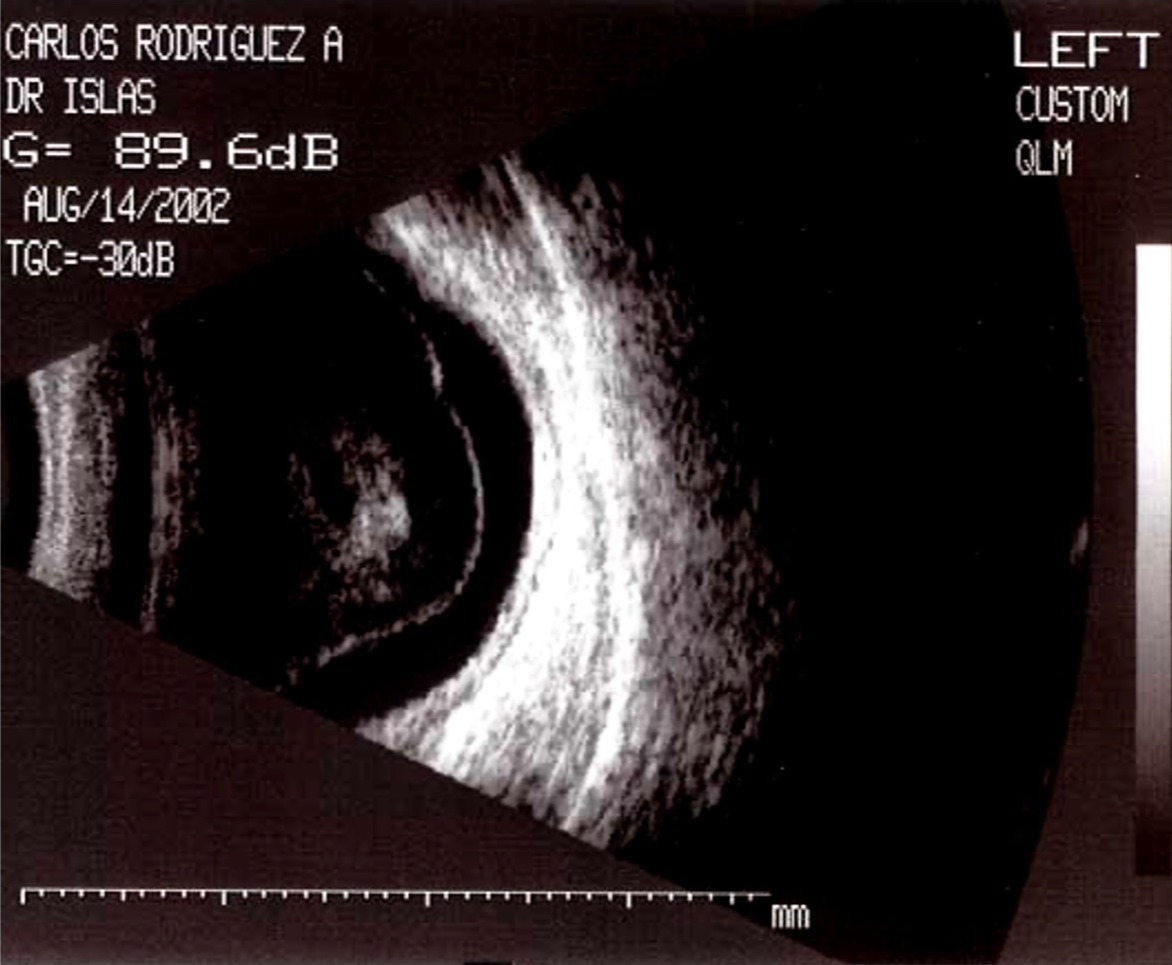

La movilidad del material ecogénico es clave:

Móvil: hemorragia vítrea reciente.

Semimóvil o fija: proliferación fibrovascular.

La inserción del plano de membranas distingue entre DPV y DRT.

El seguimiento permite valorar actividad y evolución del proceso traccional.